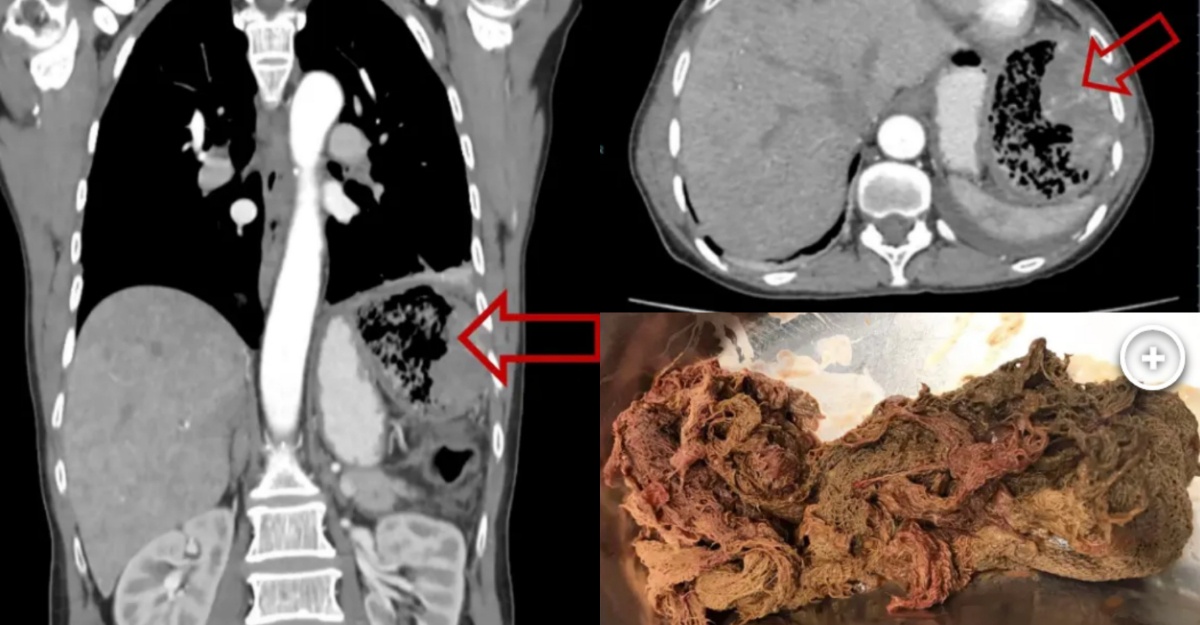

Segumpal kain kasa berjaya dikeluarkan dalam perut seorang pesakit selepas ia secara tidak sengaja ditinggalkan semasa operasi pembedahan kanser pada 20 tahun lalu, lapor New York Post.

Dilaporkan bahawa, pesakit kekal tanpa gejala selama 20 tahun walaupun terdapat kehadiran benda asing agak besar dalam rongga perutnya.

Di hospital, pegawai perubatan telah melakukan prosedur imbasan ultrasound (x-ray) dan mendapati terdapat satu gumpalan besar kain kasa di dalam perutnya.

Doktor percaya bahawa ia telah ditinggalkan di dalam perutnya semasa proses pembedahan lebih dua dekad yang lalu.

Dalam pada itu, menurut New York Post, kain tersebut telah berjaya dikeluarkan tanpa sebarang komplikasi lain dan halangan.

Gambar yang disertakan menunjukkan kain yang telah berjaya dikeluarkan kelihatan berkerak dan berubah warna kecoklatan seakan-akan pembalut mumia purba.